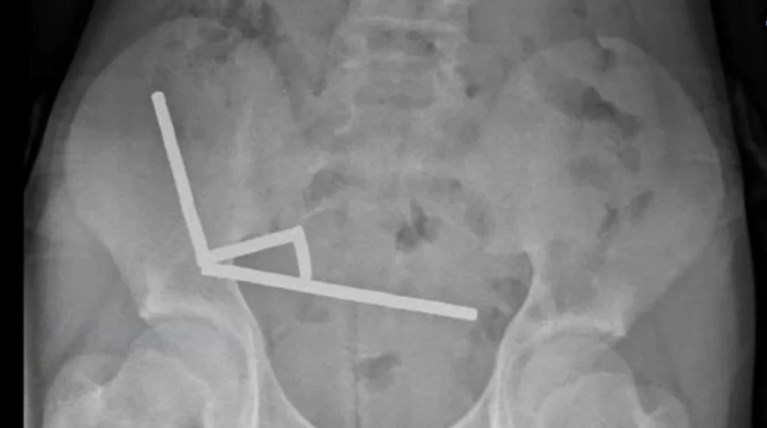

Ο έφηβος υποβλήθηκε σε επέμβαση και χρειάστηκε να του αφαιρεθούν τμήματα του εντέρου του που είχαν υποστεί νέκρωση, αφού κατάπιε μεταξύ 80 και 100 ισχυρούς μαγνήτες νεοδυμίου, μεγέθους περίπου 5Χ2 χιλιοστών, μία εβδομάδα νωρίτερα, ανέφερε η ιατρική επιθεώρηση. Έκτοτε, πήρε εξιτήριο και επέστρεψε σπίτι του.